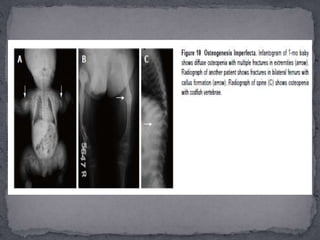

 Osteogenesis imperfecta(OI) is an autosomal dominantly or recessively inherited genetic disorder due to mutations in type 1 procollagen genes, characterised by decreased bone mass and increased bone fragility. Severity varies widely from perinatal lethality (type Ⅱ) to milder forms with minimal fractures.  Extraskeletal manifestations like blue sclerae, dentinogenesis imperfecta and deafness are also seen.  Initially, Sillence et al divided OI into four subtypes based on clinical features and disease severity:  OI type Ⅰ, with blue sclerae  OI type Ⅱ, perinatal lethal or congenital type;  OI type Ⅲ, a progressively deforming form with normal sclerae; and  OI type Ⅳ, with normal sclerae which has been further expanded to eight types.  The bone fragility increases in severity from type Ⅰ < type < Ⅴ < Ⅵ < Ⅶ < Type Ⅲ < Type Ⅷ < Type Ⅱ.

Essential radiological features: (1) Radiologically, OI is characterised by a triad of diffuse osteopenia, pencil-thin cortices, and multiple bony fractures.  The fractures are usually multiple and heal with exuberant callus formation giving rise to “pseudotumour” formation. Associated findings include deformities and pseudoarthrosis;  (2) The vertebrae are also osteopenic, have a biconcave “codfish vertebrae” appearance with areas of collapse.  (3) The skull shows multiple wormian bones, lucent calvarium, enlarged sinuses and platybasia.  (4)The pelvis is also abnormal in shape with deformities like protusio acetabuli and “shepherd crook” femurs.

 Differential diagnosesinclude 1)Battered baby syndrome, 2)Hypophosphatasia, 3) Juvenile idiopathic osteoporosis.